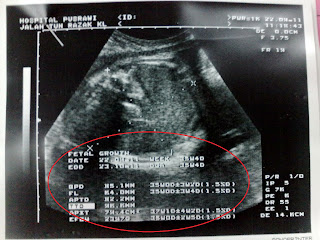

Sedu boleh berlaku bermula minggu keenam selepas konsepsi, sekalipun pergerakan pernafasan belum muncul ketika itu. Ini boleh dilihat melalui imbasan ultrasound. Teorinya, pengecutan menyediakan otot-otot respiratori bayi belum lahir untuk bernafas selepas dilahirkan.